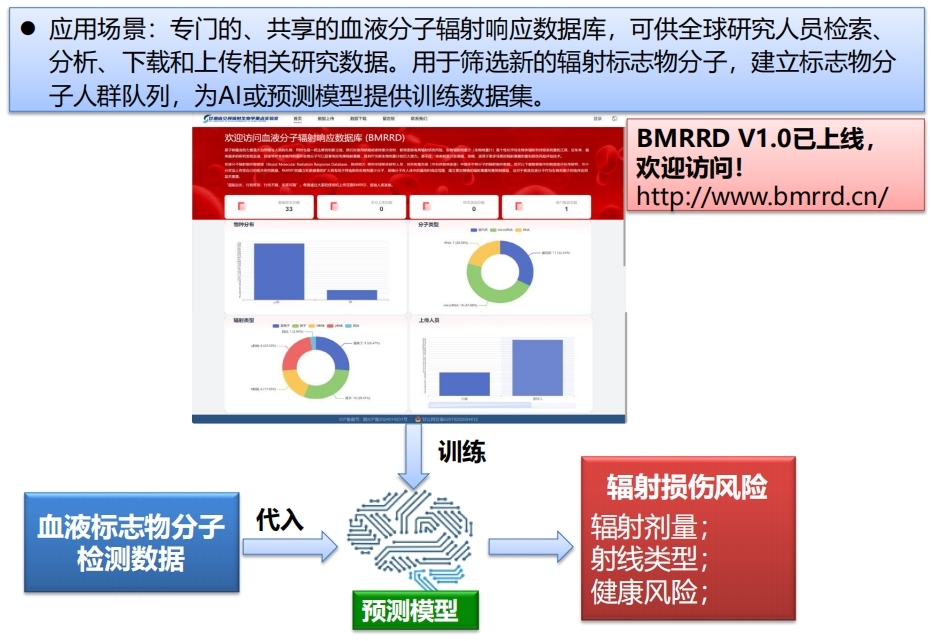

基于血液辐射标志物分子有望在未来开发便捷、准确和适用于更多场景的辐射暴露剂量和损伤风险评估技术。筛选新的生物剂量计分子、明确分子在人体中的基线和响应范围和建立更加精确的辐射暴露剂量预测模型等应用需求都需要大量的、标准化的数据,但是全球都缺乏这样一个专门的数据库。本成果建立了一个专门的、共享的血液分子辐射响应数据库(BMRRD V1.0),可供全球研究人员检索、分析和下载数据库中的数据,也欢迎上传和分享自己的相关研究数据。此外,还包含几类已经验证的数学模型,可将血液分子辐射响应数据转化为辐射暴露等级、剂量等有效信息。